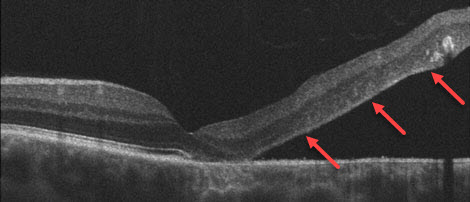

Retinal Detachment Example

Breaks in the retinal tissue (retinal holes and tears) are normally found in approximately 10% of people. In a small minority of persons with retinal breaks, liquid vitreous leaks beneath the retina, separating it from the eyewall and causing a retinal detachment. A sudden separation of the vitreous from the retina (posterior vitreous detachment) is often the inciting event causing a retinal break or detachment. Macular pucker can also develop following a vitreous detachment.